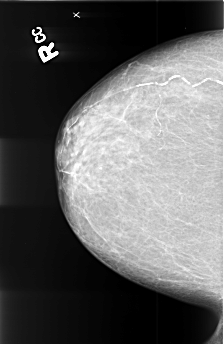

B_3413_1.RIGHT_CC

RIGHT_CC LINES 4464 PIXELS_PER_LINE 2912 BITS_PER_PIXEL 12 RESOLUTION 50 NON_OVERLAY